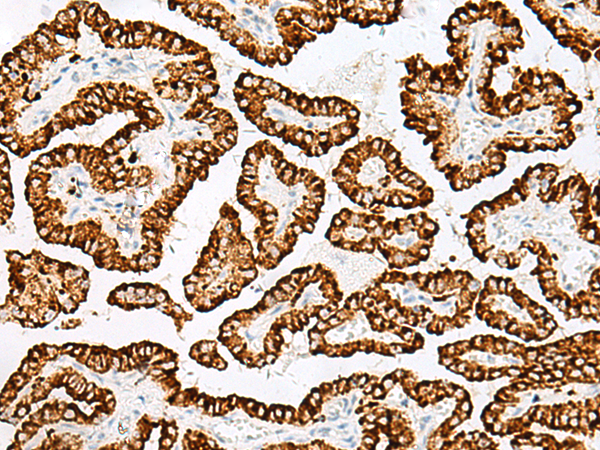

分类: 科研抗体货号: P06610别名: ENA; MENA; NDPP1应用: IHC反应种属: Human, Mouse